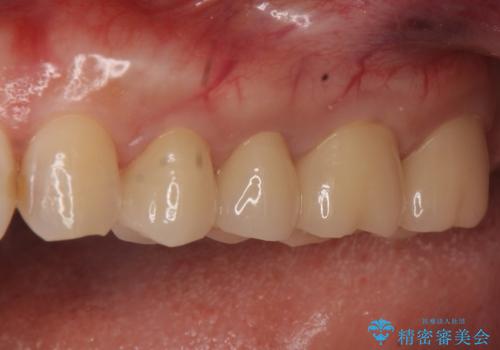

歯周病におかされた前歯の再建治療

かぶせ物の種類:PFM full bake